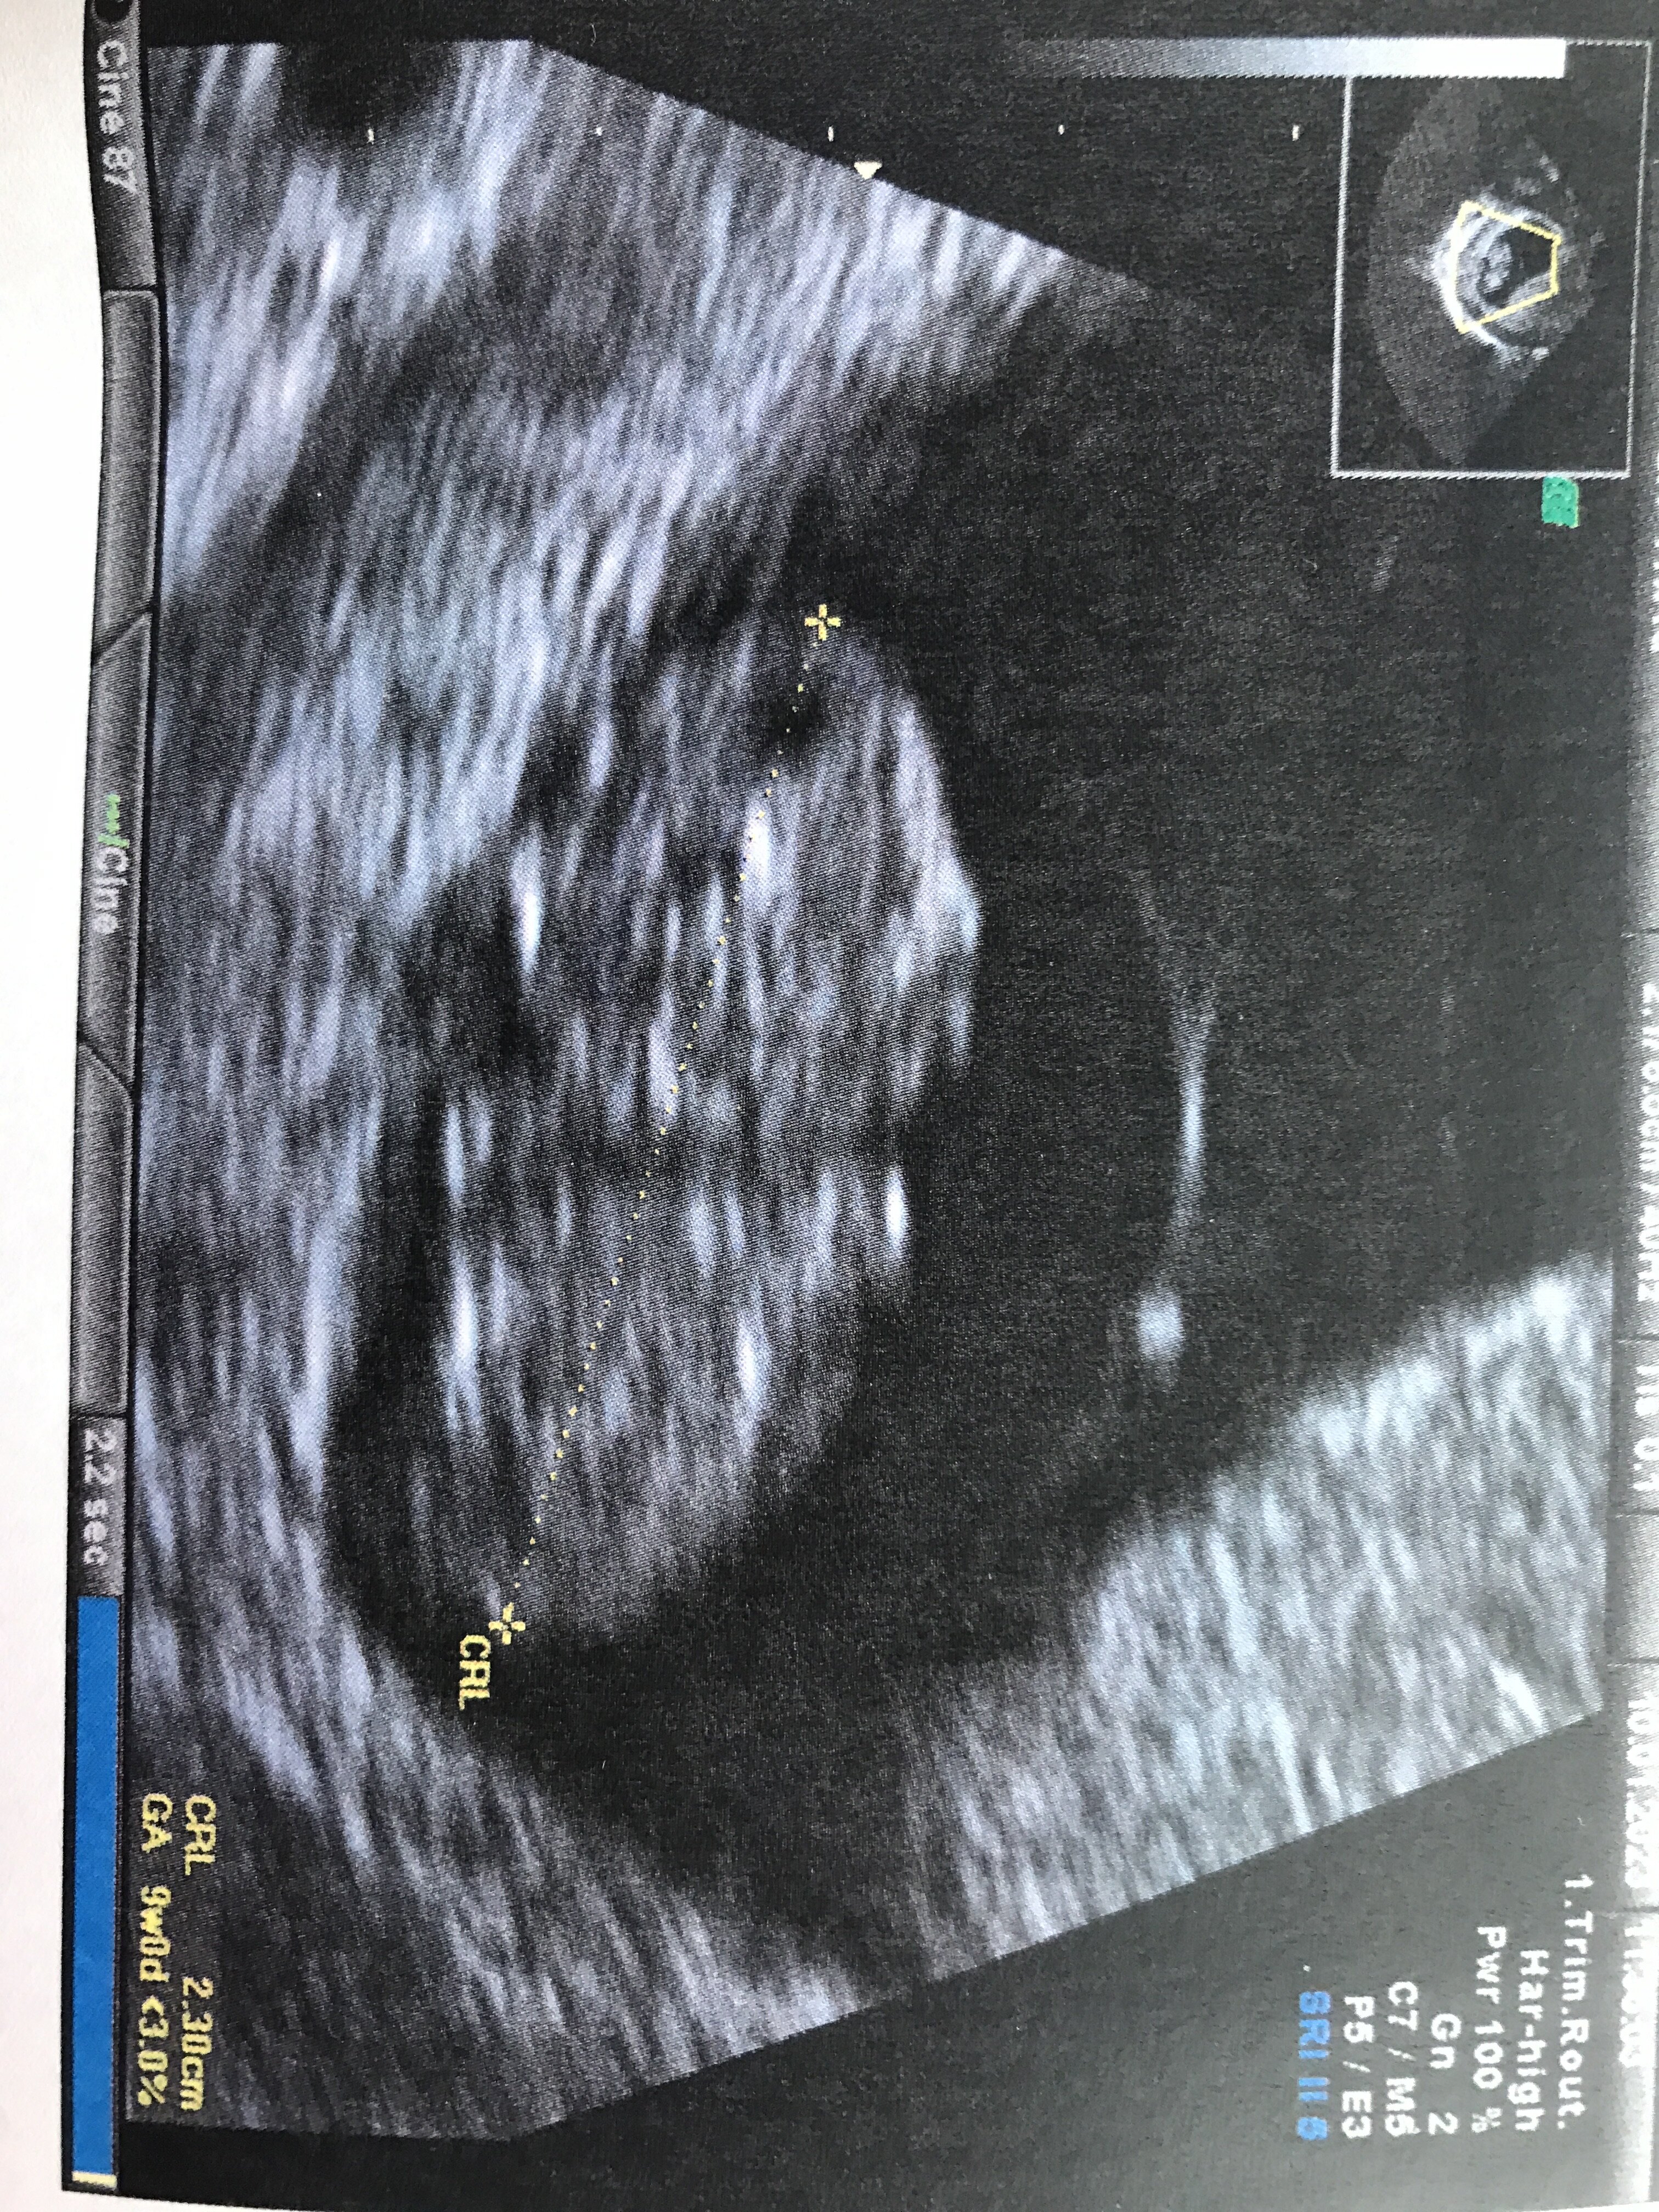

Już po wizycieWszystko jest dobrze z dzidzią

8+6/9+0

Termin porodu bez zmian możecie mnie wiec dopisać na 16.08na prenatalne umawiać się będę dopiero na następnej wizycie

Już taki duży dzidziuś